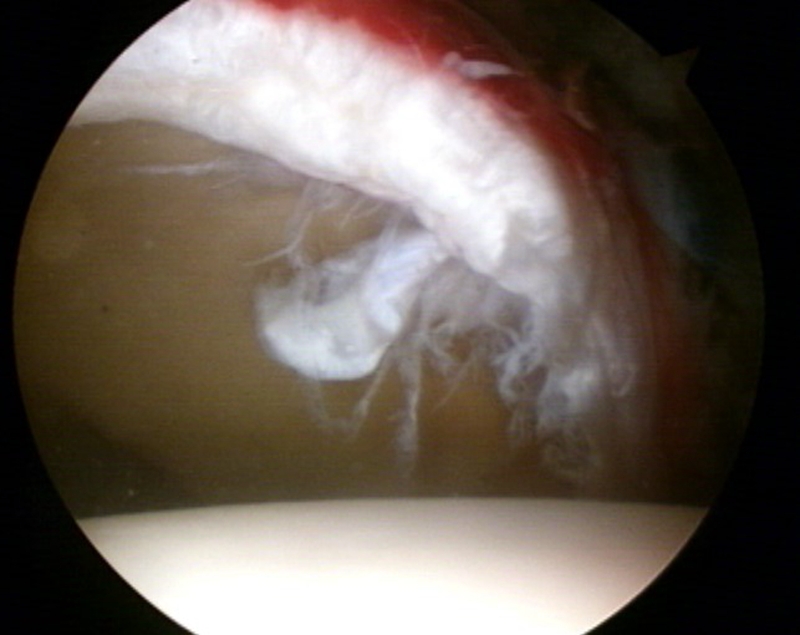

家庭不幸,首先受到伤害的就是孩子。处在髋关节这个小家庭中的盂唇也是如此。髋关节盂唇是附着于髋臼边缘的一层软组织结构,盂唇本身是有由大量的环形纤维组成,其形态与外观和膝关节的半月板类似。除了外形上,髋关节盂唇在功能上也与半月板有几分相似:首先可以增加髋臼的表面积和体积,起到加深覆盖的作用,这样髋关节可变得更加稳定;其次可以为髋关节提供负压,类似于保温杯上的“密封圈”,有了髋关节盂唇的覆盖,可以保持髋关节内的负压吸引,并保持髋关节液留在关节腔内,从而发挥其滋养髋关节表面软骨,均衡关节内应力的作用;最后,盂唇在维持关节液的平衡方面也有着重要的作用。因为处在髋臼和股骨头的中间,而且比较脆弱,当存在髋关节撞击的时候,一般首先损伤的就是盂唇。盂唇损伤在髋关节撞击综合征的患者中非常常见。

图4 髋关节镜术中图片,可见明显盂唇撕裂伴充血